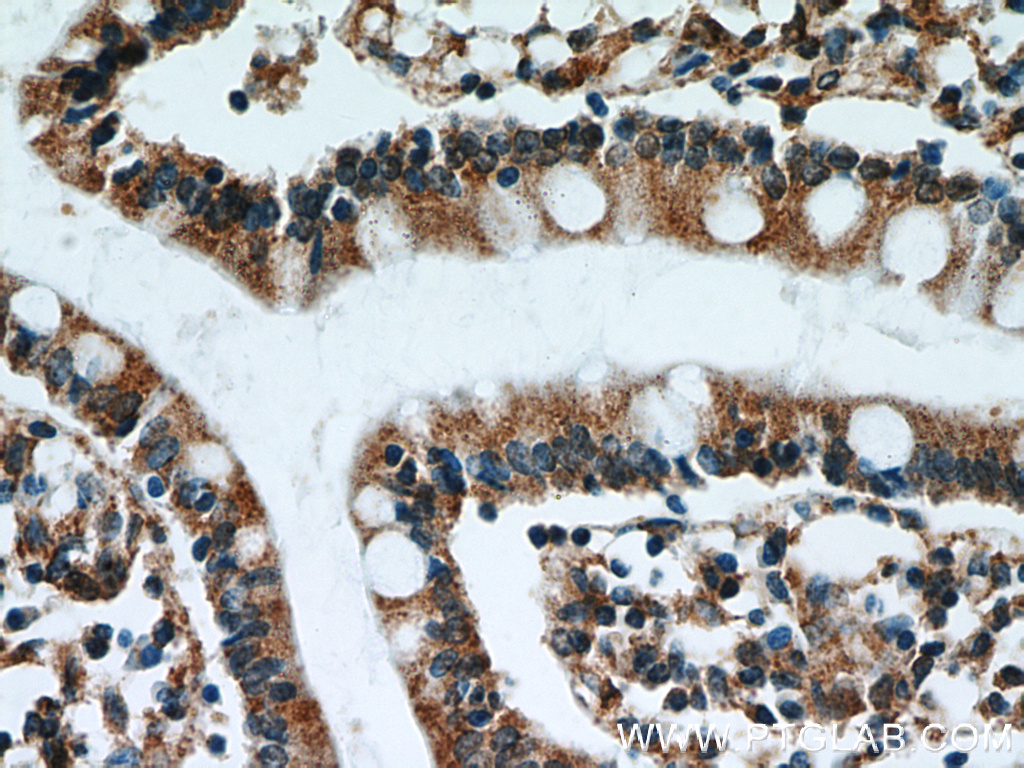

L'ATF4 intervient pour la transcription de plusieurs gènes jouant sur le métabolisme cellulaire. Son activité favorise la prolifération tumorale ainsi que la résistance aux traitements anticancéreux comme pour le cisplatine.